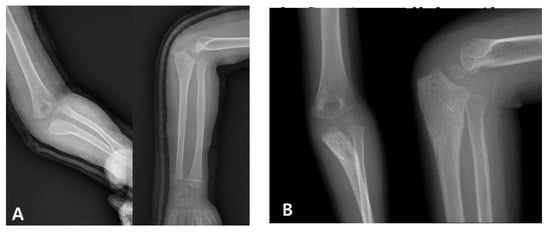

When diagnosis is delayed beyond the acute phase, the injury is considered a “neglected Monteggia fracture,” typically defined as untreated for more than two weeks. As illustrated in Figure 2, delayed treatment can result in chronic dislocation of the radial head, leading to progressive pain, valgus deformities, and a restricted range of motion [2,7]. Irreducibility due to soft tissue contracture or annular ligament entrapment may develop over time, and altered joint mechanics can result in degenerative changes and ulnar nerve dysfunction [2,8]. Surgical reconstruction (Figure 3), often involving ulnar osteotomy, open reduction, and annular ligament reconstruction, is necessary; however, the outcomes are generally inferior to those achieved with early intervention [2,9].

Figure 2. Radiographic presentation of a neglected pediatric Monteggia fracture. (A) Initial radiographs of a 4-year-old boy demonstrating a proximal ulnar fracture with anterior radial head dislocation. The injury was initially misdiagnosed as an isolated ulnar fracture, and the patient received conservative treatment at another institution. (B) Follow-up images taken after 6 weeks show fracture healing but persistent dislocation of the radial head, consistent with a neglected Monteggia fracture.